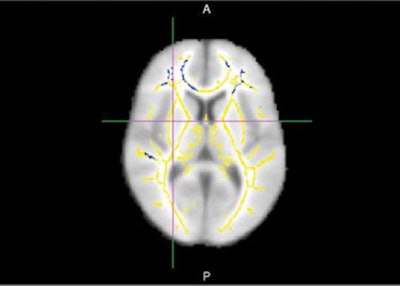

In the current study, the researchers turned to DTI to analyze white-matter integrity in the brain. The tools included fractional anisotropy, which measures the flow of water molecules along white-matter tracts. Higher fractional anisotropy values indicate normal water flow, while lower values indicate disrupted flow and the likelihood of white-matter damage.

DTI-MRI shows areas of reduced fractional anisotropy, indicating damage in the brain's white-matter tracts. Image courtesy of Dr. Cyrus Raji and RSNA.Of the 20 patients, half experienced cognitive decline and Alzheimer's disease over various time points up to several years, and half remained cognitively normal. Among the global DTI measures, differences in fractional anisotropy corresponded with progression to Alzheimer's disease, the researchers found. Radial, axial, and mean diffusivity did not show any significant differences, they noted.